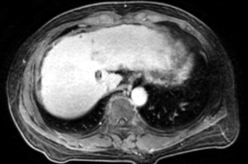

Ø 术前影像学检查

肝 S2 段及肝 S4 段见类圆形 T1WI 低、T2WI-SPAIR/DWI/ADC 高信号,较大者长径

约 10mm,界清。

动脉期

静脉期